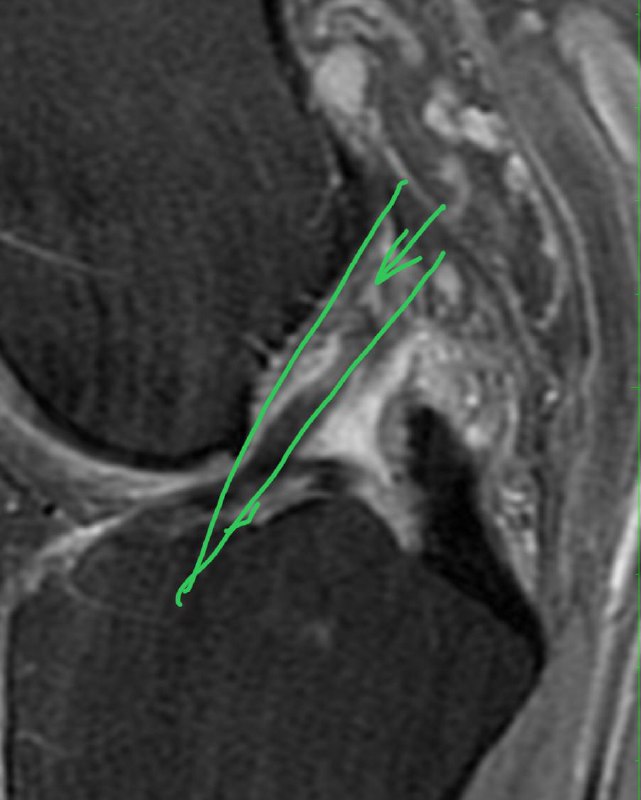

Разрыв передней крестообразной связки. Угол между ней и крышей межмыщелковой ямки открыт не вперед, а назад.